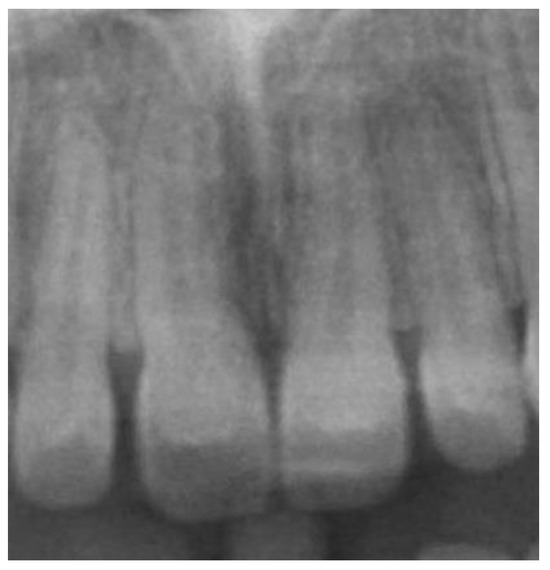

2.2. Data Acquisition and Measurements

- Distance between the most mesial point of the root and the tangent passing through the most anterior point of the incisive canal—|Rm-Cat|.

- Distance from Cl to the posterior edge of the incisor root—|Cl-Rpt|.

- Distance between roots |Rm-Rm|.